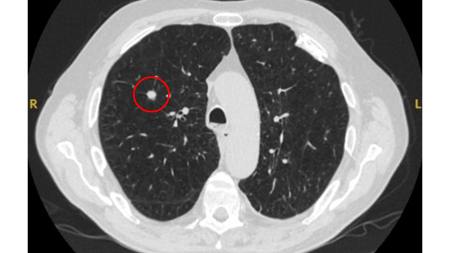

Computed tomography (CT) showing a posterior left upper lobe spiculated nodule, with ‘bronchus sign’ in a female non-smoker. Bronchoscopic forceps biopsy and brushing assisted by radial EBUS miniprobe localisation, confirmed a non-Hodgkin’s lymphoma

From the collection of Dr George Tsaknis, MD, PhD, FRCP(London), MRQA, MAcadMEd, PGCert; used with permission